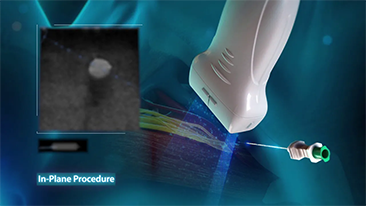

W zwi?zku z pandemi? koronawirusa szpitale i personel medyczny opracowa?y nowe praktyki robocze obejmuj?ce post?powanie w sytuacjach dotycz?cych stanów ostrych, dystans spo?eczny, rygorystyczne stosowanie ?rodków ochrony indywidualnej (?OI), mycie r?k i codzienn? dezynfekcj? sprz?tu. Dodatkowo w punktach opieki medycznej coraz wi?ksze znaczenie zacz?? mie? przeno?ny, wysoce mobilny i wszechstronny sprz?t, przydatny zw?aszcza w sytuacji, gdy oddzia?y i bloki operacyjne s? rozmieszczone na kilku pi?trach, a dost?p do specjalistycznych urz?dzeń jest ograniczony.